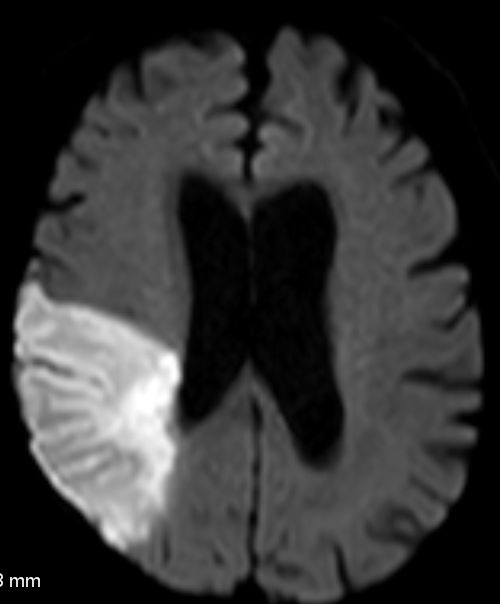

MRT spezielle Sequenzen für den Apoplex: DWI,PWT 76-jähriger Mann mit frischem Apoplex. Ausfall des hinteren Mediabereiches rechts. MR DWI og tra Sense

MR DWI EADC

DWI Diffusion weighted imaging